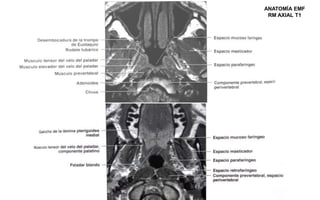

ANATOMÍA EMF

RM AXIAL T1